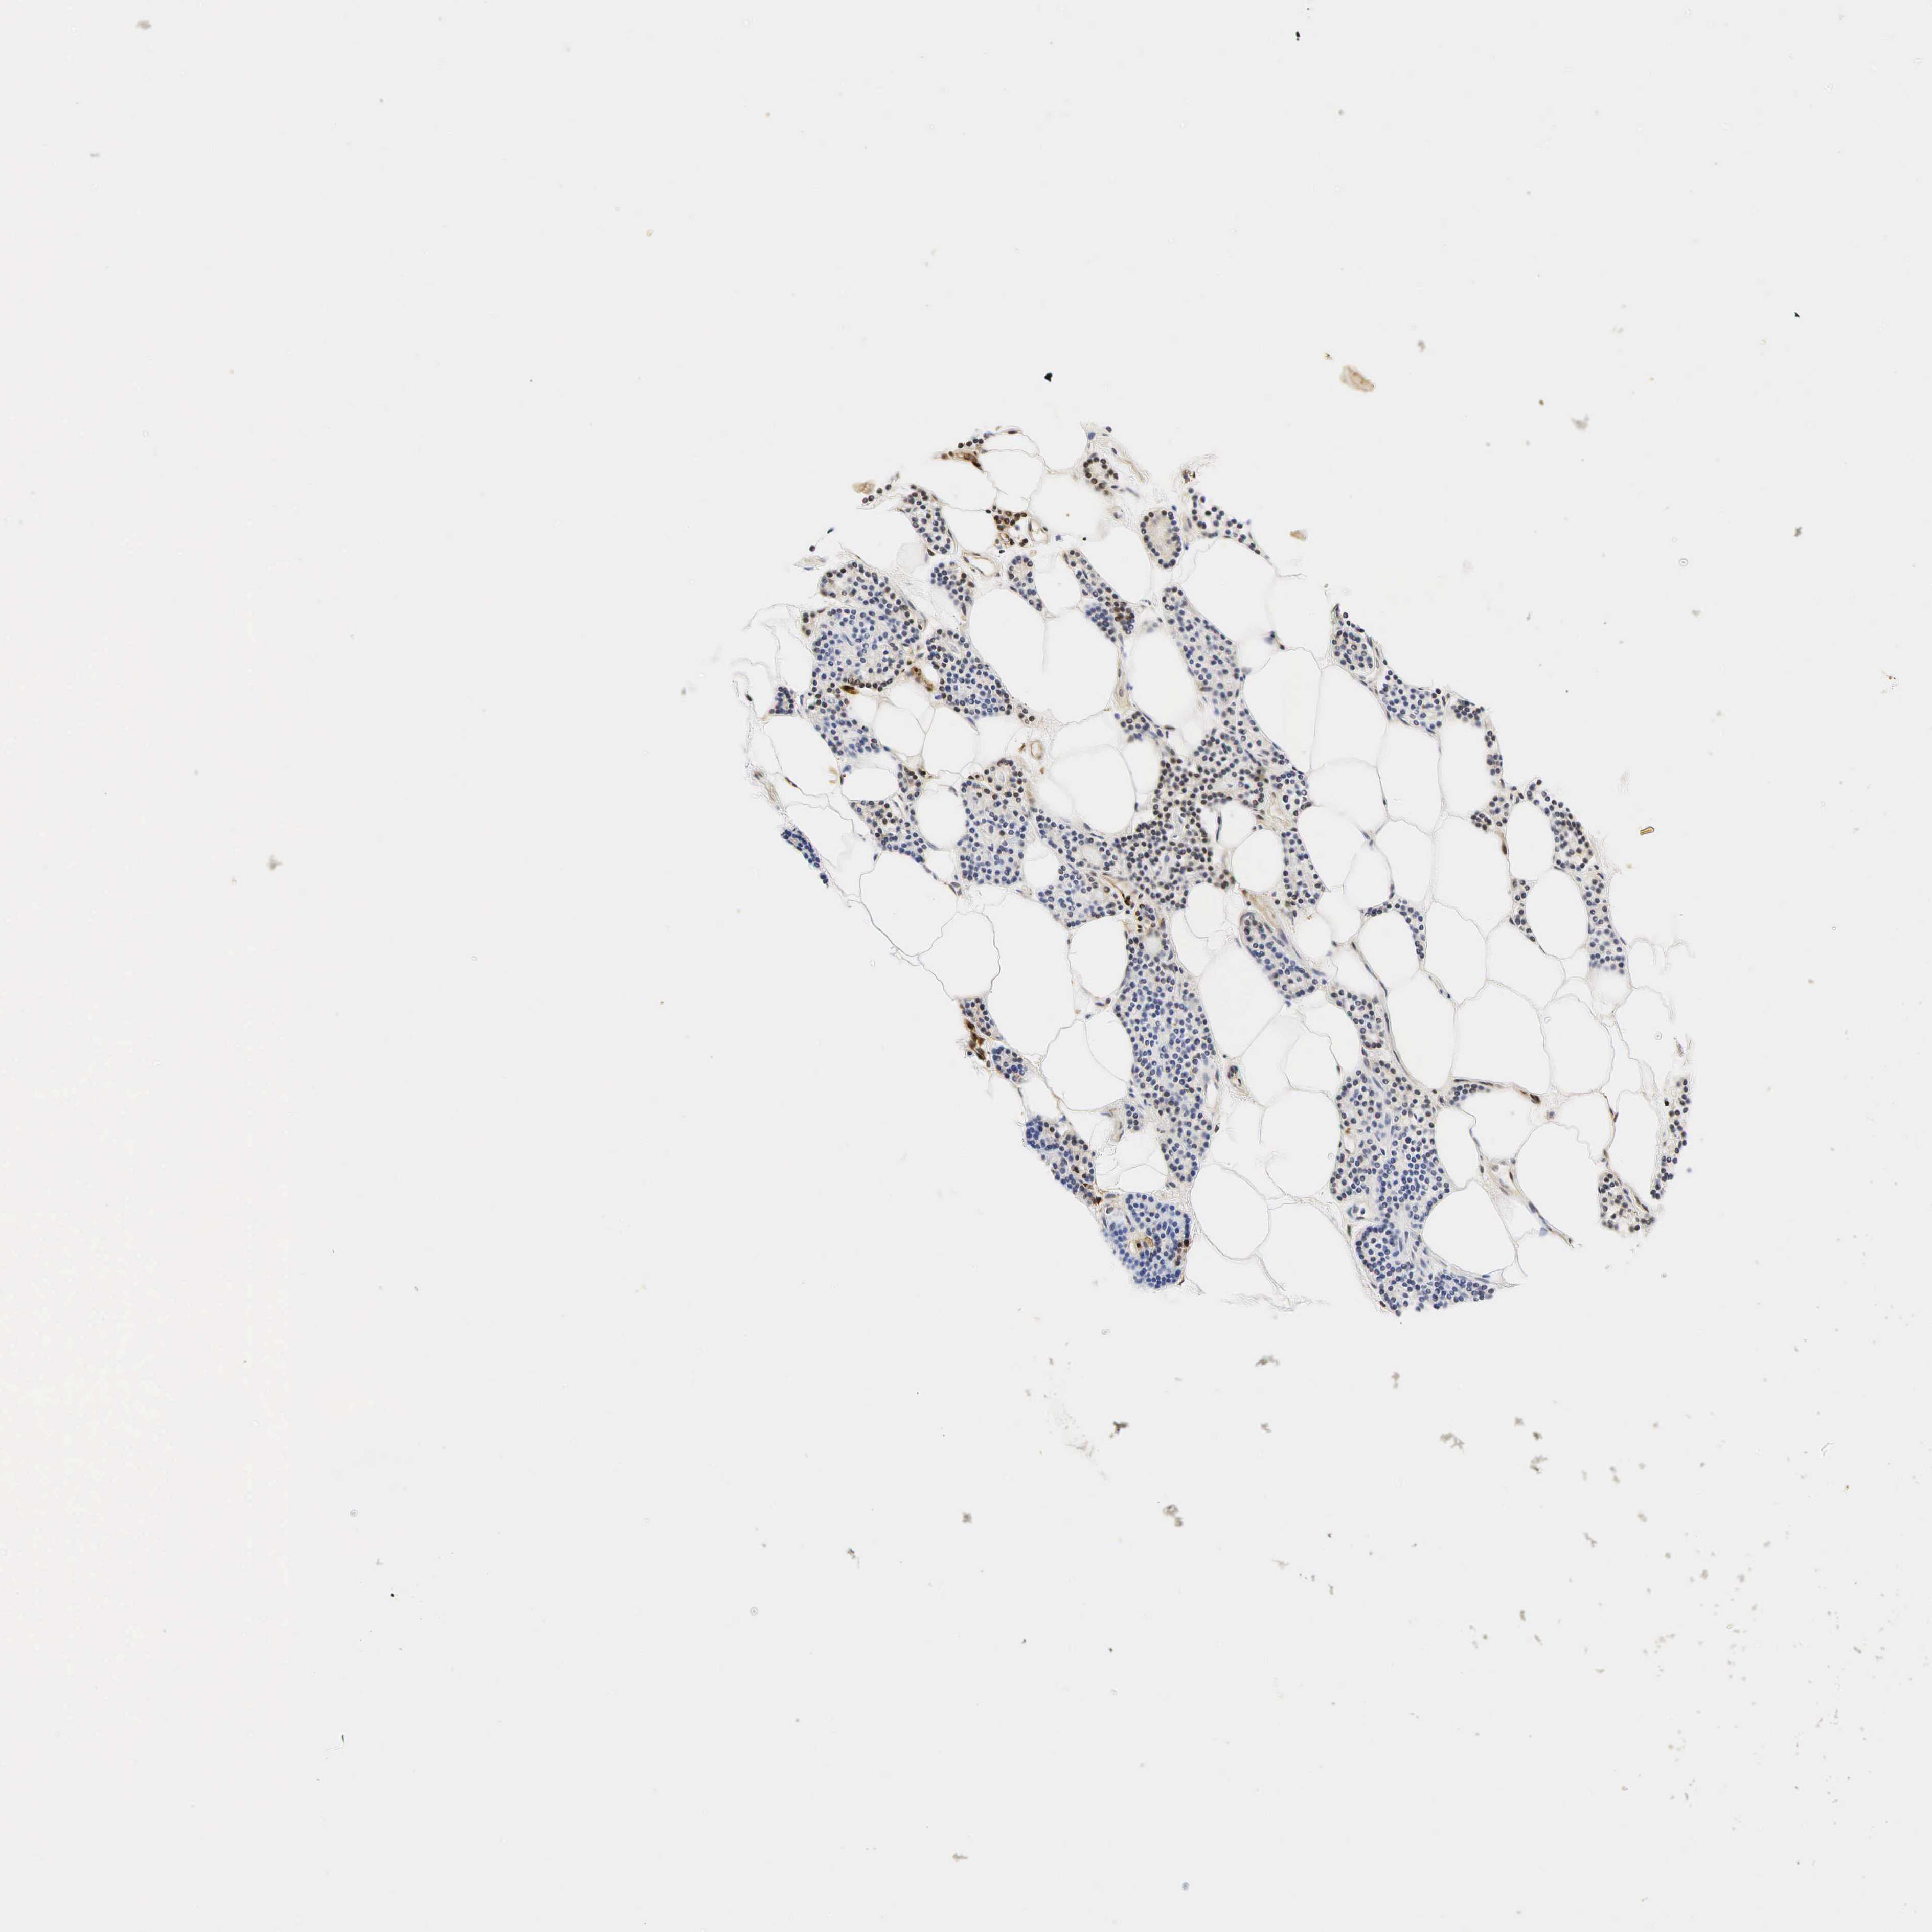

TISSUE PRIMARY DATA PARATHYROID GLAND Show tissue menu

Parathyroid gland

PARATHYROID GLAND - Expression summary

PARATHYROID GLAND - Antibody stainingi

Antibody staining in the annotated cell types in the current human tissue is reported as not detected, low, medium, or high, based on conventional immunohistochemistry profiling in selected tissues. This score is based on the combination of the staining intensity and fraction of stained cells.

Each image is clickable and will lead to virtual microscopy that enables deeper exploration of all samples and also displays staining intensity scores, fraction scores and subcellular localization as well as patient and tissue information for each sample.

Antibody HPA048284Antibody CAB000055

Glandular cells Not detectedNot detected